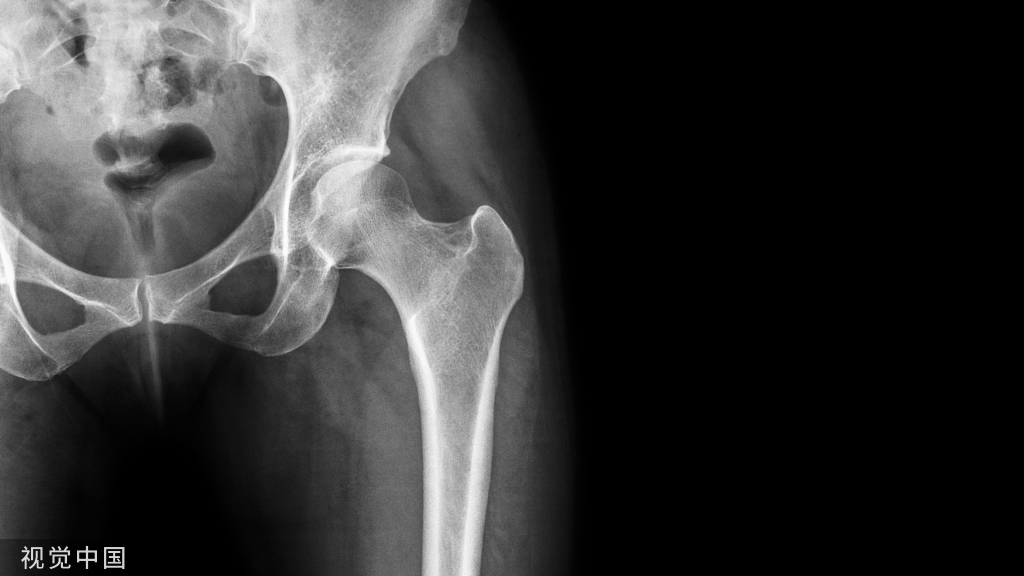

髋关节测量方法!